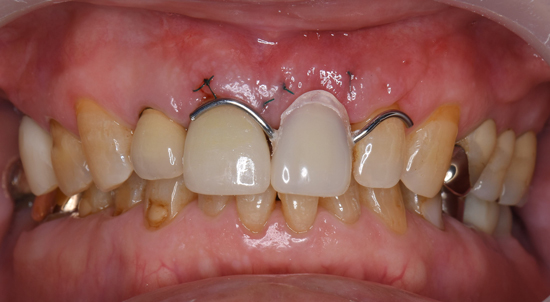

患者様は、抜歯した同日に、インプラント移植と、骨の増強を一度に行う治療を選択されました。また、仮歯を付けて帰る事も希望されました。

手術当日の仮歯。わざと、薄く、短く仕上げています。

手術から3ヶ月後の状態。色見本を参考にしながら、セラミックの前歯を最終完成させていきます。

指示したインプラントの前歯が完成してきました。どのような仕上がりになっているのか、ワクワクします。

手術時の傷口は、キレイに治っています。インプラントを装着する部分の歯肉だけが円状になっています。

完成です。インプラントのおかげで、歯を削らずにすみました(ブリッジ)。入れ歯の金具もありません。他の歯に迷惑をかけることなく、前歯が再び、独立、誕生しました。